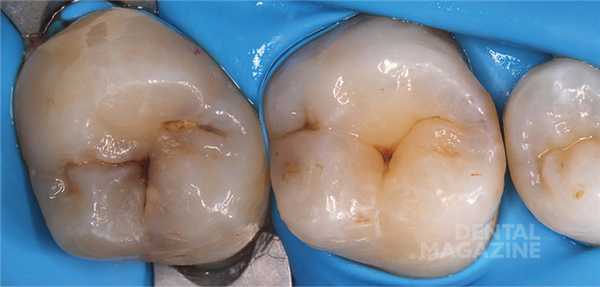

После изоляции рабочего поля (рис. 2) и механической отчистки от налета с поверхности зубов снимается ключ bite-силиконом с учетом габаритов клампа (рис. 3) .